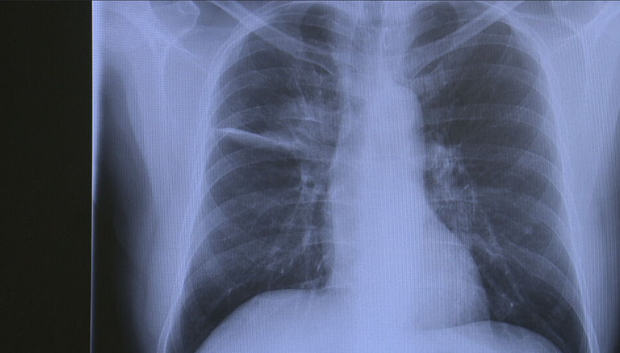

Camidge explained he first noticed he had a wheeze and shoulder pain, symptoms he chalked up to asthma or a pulled muscle. Yet an X-ray revealed otherwise.

"Within about four days, I had gone from saying, 'Oh, maybe I pulled something at the gym,' to knowing that I had stage four, advanced incurable lung cancer," he said.